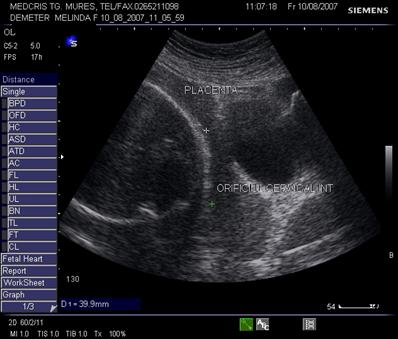

Fig. nr.206. Placenta normal inserata pe peretele anterior uterin , cu marginea sa inferioara la 4 cm de orificiul cervical interin

Diagnosticul ecografic se face urmarind marginea placentara inferioara si raportul cu orificiul cervical intern. O imagine mai buna necesita vezica urinara in semipletie sau chiar o ecografie transvaginala.

Fig. nr.217. Placenta praevia centrala la 15 saptamani ( linia indica raportul placenta praevia cu orificiul cervical intern)

Fig. nr.218. Placenta praevia complet centrala , la aceeasi sarcina ca in figura precedenta, dar la 28 saptamani gestationale

Fig. nr.219. Placenta praevia marginala , la nivelul orificiului cervical intern marcat cu linie, se observa marginea inferioara a placentei, inserata pe peretele uterin anterior